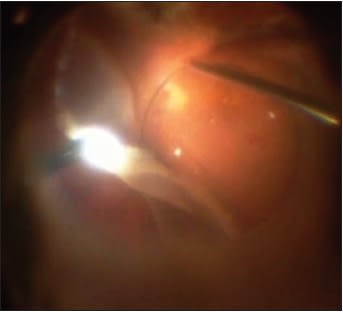

Perfluoron displaces subretinal fluid anteriorly. Therefore, during Perfluoron infusion, the eye should be rolled so that any retinal defect, such as a retinotomy or retinal tear, is as anterior as possible. Then, as the Perfluoron is injected into the vitreous cavity, the retinal defect remains open, allowing egress of displaced subretinal fluid (Figure 1). If Perfluoron occludes the retinal defect before all the posterior subretinal fluid drains, a pocket of subretinal fluid will be trapped posteriorly, preventing complete intraoperative retinal attachment. That trapped subretinal fluid makes retinal slippage more likely when Perfluoron is removed from the eye.

Figure 1. Intraoperative photograph of Perfluoron bubble on macula with retinal detachment and retinotomy on the left of photo.